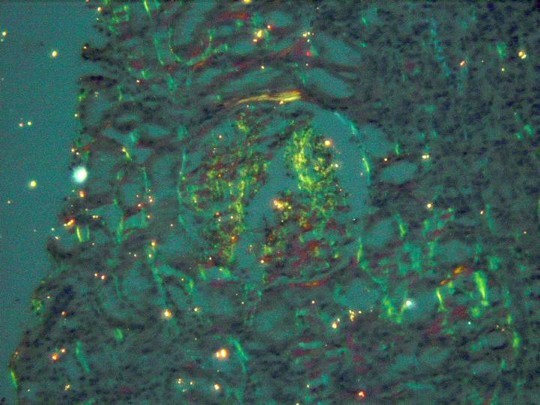

RW is a 60 yr old male who has been on renal dialysis for the past 15 years. His urinary protein electrophoresis is notable for light chains. Based on his history and the histology below (under polarized light), what is his diagnosis?

A collection of diseases sharing a common feature:

- common feature = Extracellular deposition of pathologic insoluble fibrillar proteins

- Protein deposition impairs normal function

Multiple organs and tissues can be involved

Virchow coined the term amyloid, meaning starch like

** Chronic Renal dialysis–> alpha-2-beta globulin deposition

Histo:

Light microscope:

- Amorphous deposition of pink material around glomeruli, afferent, efferent arterioles

- Congo red positive, Not PAS positive